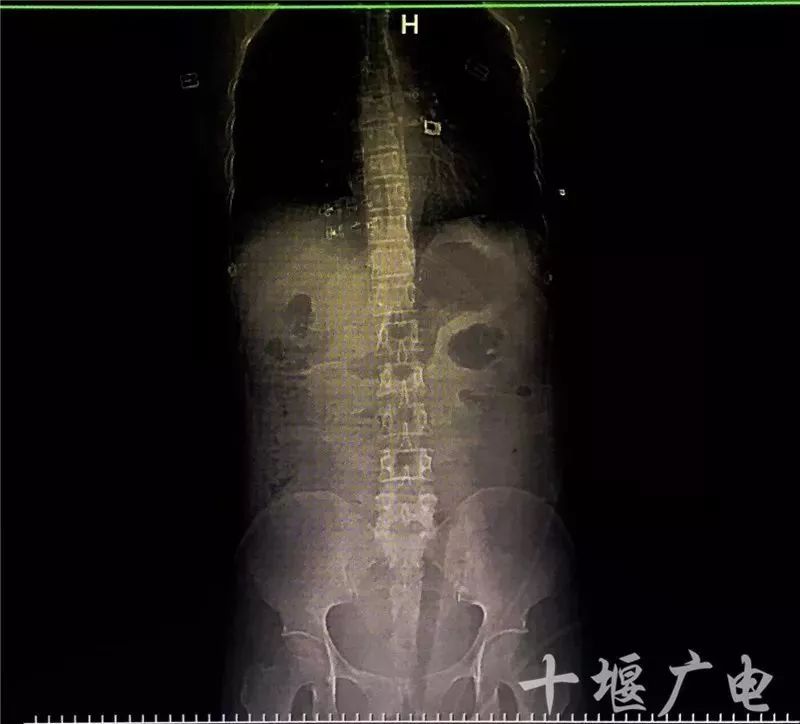

拍片子检查发现,闵先生的4节腰椎受损,椎体的横突部位均发生断裂,幸运的是没有损伤到神经。接诊的杨启超医生为闵先生进行了腰围固定,并打了止痛针。